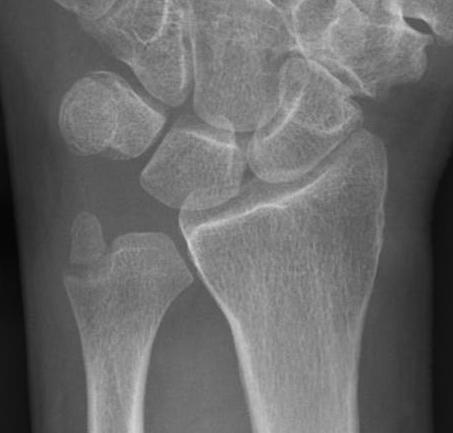

Xray

True lateral

- radial styloid overlies proximal scaphoid / lunate / triquetram

Dorsal subluxation of the distal ulna